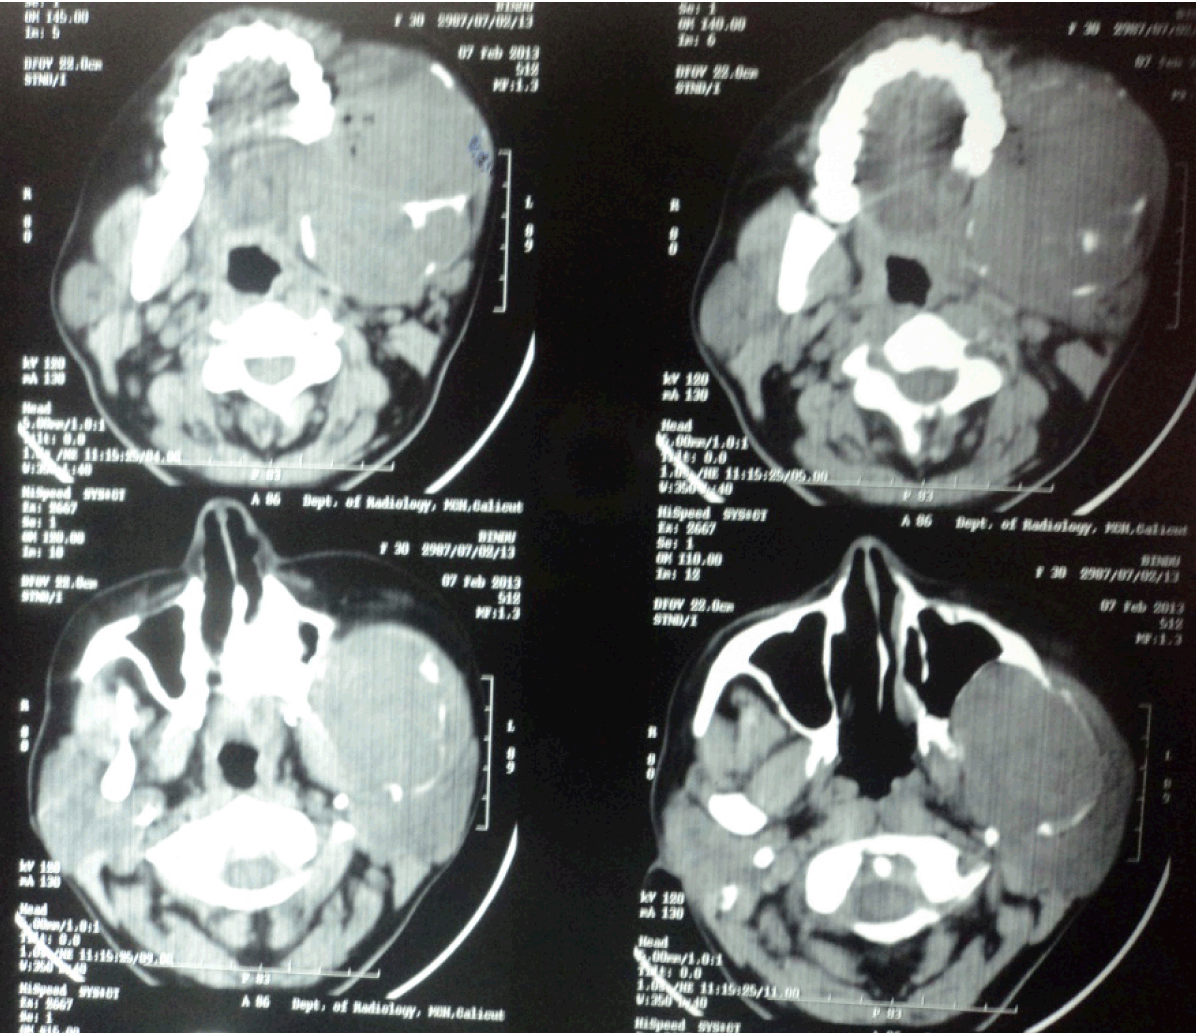

The orthopantomograph (OPG) showed a well-defined radiolucency involving the left body, angle and ramus of the mandible (Figure 3). The OPG revealed root resorption of left lower first molar tooth. Plain and contrast axial and coronal computed tomography (CT) scans showed a lobulated expansile lytic lesion involving body, ramus, and coronoid process of mandible measuring 6.3x8.3x10 cm in size, with thinning of the cortices (Figure 4). A chest radiograph ruled out the presence of any metastatic deposits. An incisional biopsy was done and the tissue was sent for histopathologic examination. The histopathology was consistent of ameloblastic carcinoma (Figure 5). On the basis of the histopathology report, left hemimandibulectomy was done taking a safe margin of 2 cm and the defect was reconstructed using Titanium reconstruction plate. Chemotherapy and radiotherapy was not advised. The patient is under regular follow-up. No recurrence or metastases reported during the follow-up period.

Figure 4: Computed tomography (CT) scan showing the lesion.